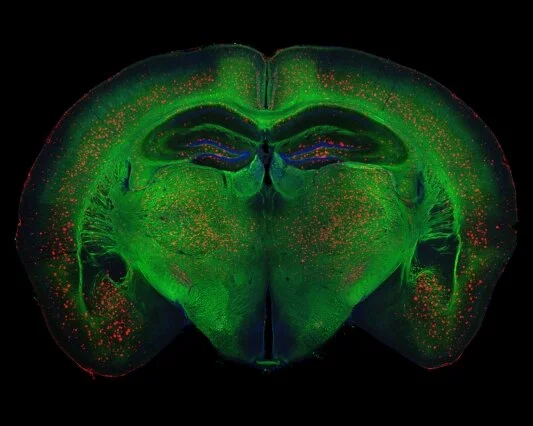

by Fran Lowry for Medscape:The presence of TAR DNA-binding protein 43 (TDP-43) in the hippocampus on postmortem examination is associated with increased rates of hippocampal atrophy in patients with Alzheimer's disease (AD), new research suggests.This association was greatest in individuals who had an intermediate or high likelihood of having AD (ie, neurofibrillary tangle stages B2 and B3), but not in those with a low likelihood (neurofibrillary tangle stage B1) of having AD.Moreover, increased rates of TDP-43–associated hippocampal atrophy could be detected at least 10 years before death.The findings were published online September 11 in Lancet Neurology."This is the first time in the history of Alzheimer's that a protein has been shown to correlate with shrinkage of this part of the brain, so TDP-43 could be a target, something we could direct medication towards, perhaps," lead author, Keith Josephs, MD, Mayo Clinic, Rochester, Minnesota, told Medscape Medical News. "It is quite possible that this could be one of the treatments for Alzheimer's in the future."In a longitudinal retrospective study, Dr Josephs and colleagues analyzed postmortem brain tissue of 298 individuals with an AD-spectrum pathologic diagnosis who had undergone head MRI between January 1, 1999, and December 31, 2012.The patients had been recruited into the Mayo Clinic Alzheimer's Disease Research Center, Mayo Clinic Alzheimer's Disease Patient Registry, or the Mayo Clinic Study of Aging.The researchers performed TDP-43 immunohistochemistry and classified individuals as follows: no TDP-43 in the amygdala or hippocampus, TDP-43 restricted to the amygdala, and TDP-43 spreading into the hippocampus.Each individual was also assigned a neurofibrillary tangle stage (B1 to B3), relating to the likelihood of having AD.Hippocampal volume was calculated on all serial MRI scans, and links between TDP-43 and rate of hippocampal atrophy were calculated.Of the 298 patients, 141 showed no TDP-43 in the amygdala or hippocampus, 33 had the protein in the amygdala only, and 124 patients had TDP-43 in the hippocampus.Among patients at high likelihood of having AD, those who had hippocampal TDP-43 had faster rates of hippocampal atrophy compared with those who had TDP-43 in the amygdala only and those with no TDP-43.Their annual volume change was –4.39% (95% confidence interval [CI], –4.82% to –3.95%; P < .0001). In comparison, those who had TDP-43 in the amygdala only had an annual volume change of –3.29% (95% CI, –4.11% to –2.46%; P < .0001) and those without TDP-43 had an annual volume change of –3.11% (–3.54% to –2.68; P < .0001).A similar trend was seen in patients with an intermediate likelihood of having AD (neurofibrillary tangle stage B2). Those who had hippocampal TDP-43 had faster rates of hippocampal atrophy, with an annual volume change of –4.05% (95% CI, –5.09% to –2.99%; P < .0001).Those with TDP-43 in the amygdala only had an annual volume change of –1.78% (95% CI, –3.04% to 0.55%; P = .004), and those with no TDP-43 had an annual volume change of –1.63% (95% CI, –2.43% to –0.83%; P = .0002).Hippocampal TDP-43 was not associated with the rate of hippocampal atrophy in individuals with a low likelihood of having AD (those with neurofibrillary tangle stage B1).The trajectory analysis suggested that increased rates of TDP-43–associated hippocampal atrophy might occur at least 10 years before death.Currently, no clinical trials are targeting TDP-43, but Dr Josephs hopes this will change."Other clinical trials targeting the two other proteins that we see in AD, amyloid and tau, have all failed. No treatment trial has so far shown any benefit when tau and amyloid have been targeted, but no one has targeted TDP-43, so this would certainly be worth a try."Useful Target?"This is an interesting paper that contributes to our understanding of Alzheimer's disease," Keith Fargo, PhD, director of scientific programs at the Alzheimer's Association in Chicago, Illinois, told Medscape Medical News."Time will tell the significance of this protein. It would be great if it would be a useful target, but you can't know based just on the strength of this paper whether it will turn out to be that way or not. But the results of this paper are consistent with the thought that it may potentially be a target for therapeutics for Alzheimer's disease," Dr Fargo said.TDP-43 does seem to be important in several other neurodegenerative diseases as well, such as amyotrophic lateral sclerosis and frontotemporal dementia, Dr Fargo noted."There are lot of things we still don't know about Alzheimer's disease," he said. "Why does one person get it and not another? What could cause people who have amyloid to go on to develop tau, and then go on to develop that neurodegeneration?"This work gives us more information about what is actually causing the loss of brain cells. It opens up new potential targets for treatment and at the very least helps us understand the disease course better."Source: http://wb.md/2wPtmWl